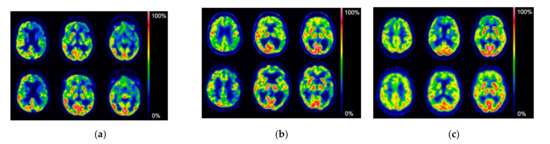

3. Results

3.3.1. Intrapatient Correlation Analysis

3.3.2. Interpatient Correlation Analysis